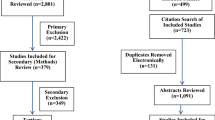

ACL autograft signal intensity was measured in 17 male patients (age, 28.3 ± 7.0 years) who underwent ACL reconstruction with hamstring autograft at 6 weeks, 3-, 6-, 12-, and 24 months postoperatively by 3 Tesla MRI. Controls with an intact ACL served as control group (22 males, 8 females; age, 26.7 ± 6.8 years). An ACL/PCL ratio (APR) and ACL/muscle ratio (AMR) was calculated to normalize signals to soft tissue signal. APR and AMR were compared across time and to native ACL signal. Clinical outcome scores (IKDC, Lysholm), return to preinjury sports levels (Tegner activity scale), and knee laxity measurement (KT-1000) were obtained and correlated to APR and AMR at the respective time points.